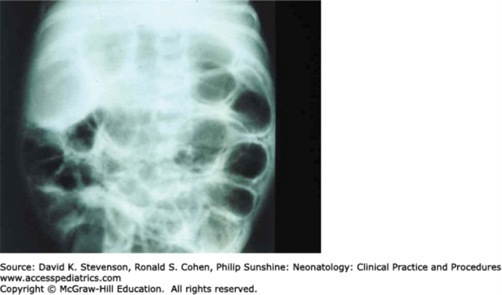

A male infant born at 25 2/7 weeks' gestation (birth weight 800 g) develops tachycardia and abdominal distension prior to passing a blood-tinged stool. His physical examination reveals decreased tone and activity, tenderness on palpation of the abdomen, and a paucity of bowel sounds. His abdominal x-ray shows diffuse pneumatosis without pneumoperitoneum or portal venous air. His parents arrive during initial stabilization of their infant and ask to speak to the attending neonatologist.

Explanation: Necrotizing enterocolitis (NEC) occurs most commonly in premature infants. The incidence of NEC is inversely related to 2 important risk factors: birth weight and gestational age. In addition, the risk of mortality from NEC is higher for the smallest infants born at lower gestational ages. Mortality is also related to the need for surgical intervention, and the extent of bowel involvement, with survival directly related to the length of remaining bowel after surgical resection. Even in the absence of surgical intervention, NEC increases the incidence of other prematurity-related complications, including chronic lung disease, growth failure, neurodevelopmental delays, and hospital-acquired infections. Additionally, infants with NEC who require surgery have a greater risk of neurodevelopmental impairment (2-3 times greater risk than infants managed with medical therapy alone). There is no evidence to suggest that hypersensitivity to breast milk is involved in NEC pathophysiology. Strictures may occur weeks to months after an episode of NEC, even in the absence of bowel perforation.